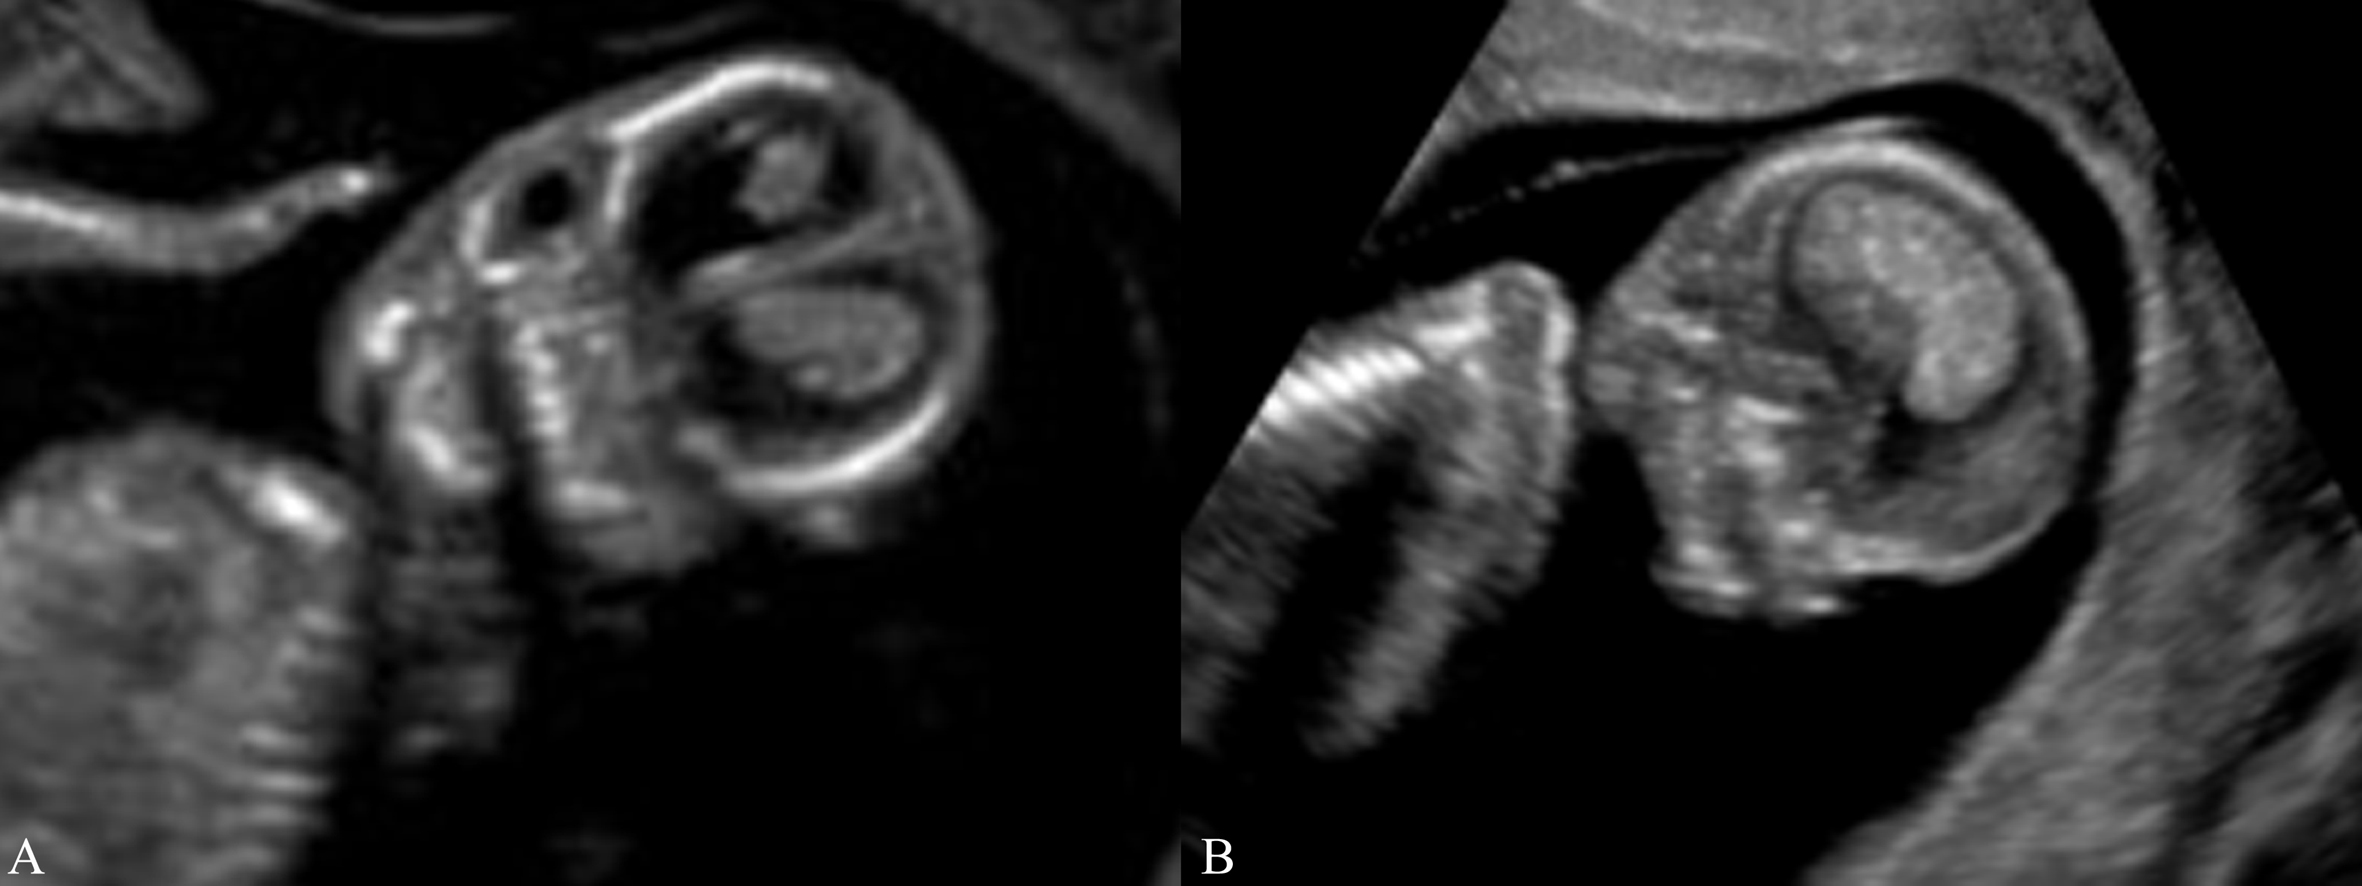

妊娠第7周后胚胎头部可见脑泡显示,妊娠第9孕周时胚胎头部的侧脑室、第三脑室、第四脑室共同构成了胚胎颅内囊性结构。超声显像检查显示颅内大部分均为无回声,不可误认为脑积水。第11~12孕周后侧脑室明显扩大,甚至接近颅骨内侧板。在超声显像检查中大脑皮质仅显示为侧脑室表面的环状低回声带;在侧脑室内,除了前角内,几乎均可见到由脉络丛形成的强回声(图1)。这种情况大约在第 20孕周以后消失。

图1 胚胎及胎儿颅内无回声及脉络丛回声(A:8周胚胎 B:12周胎儿)